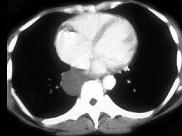

问题 男,42岁,轻度咳嗽,胸部隐痛2月余,请结合CT检查,选出最可能的诊断 ( )

选项 A.食管囊肿 B.淋巴管囊肿 C.淋巴管瘤 D.支气管囊肿 E.神经源性肿瘤

答案 D